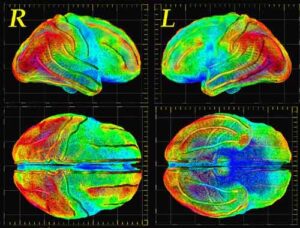

PER LA PRIMA volta è stata individuata nel cervello la ‘firma’ del dolore e il risultato potrebbe portare allo sviluppo di metodi affidabili per quantificare in modo oggettivo il dolore dei pazienti. Tutto questo è possibile analizzando immagini del cervello scattate a un gruppo di volontari mentre sentivano dolore. Il test è stato portato avanti da un gruppo di ricerca americano coordinato dall’università del Colorado a Boulder. La ricerca, pubblicata sulla rivista New England Journal of Medicine, può inoltre porre le basi per lo sviluppo di metodi che utilizzano scansioni del cervello per misurare oggettivamente ansia, depressione, rabbia o altri stati emotivi. “In questo momento – ha osservato il coordinatore del lavoro, Tor Wager – non c’è un metodo clinicamente accettabile per misurare il dolore e altre emozioni diverse se non chiedere a una persona come si sente”. Attualmente, infatti, l’intensità del dolore può essere misurata solo in base alla descrizione di un paziente, che spesso include la classifica del dolore su una scala da uno a 10.

Per arrivare alle loro conclusioni, i ricercatori hanno esaminato le immagini di 114 cervelli scattate quando i volontari sono stati esposti a livelli di calore, che vanno da benignamente caldo a dolorosamente caldo.

E’ stato così possibile identificare una firma distinta neurologica del dolore fisico e i ricercatori sono stati sorpresi di vedere che questa ‘firma’ è la stessa in tutte le

persone: si aspettavano, invece, che sarebbe stata unica per ogni individuo. Questo permette di prevedere quanto dolore una persona sta avvertendo con un’accuratezza compresa fra il 90 e il 100 per cento. E’ stata anche una sorpresa scoprire che tale ‘firma’ era specifica per il dolore fisico. Secondo studi precedenti, invece, la sofferenza psicologica può apparire molto simile al dolore fisico in termini di attività cerebrale che produce.